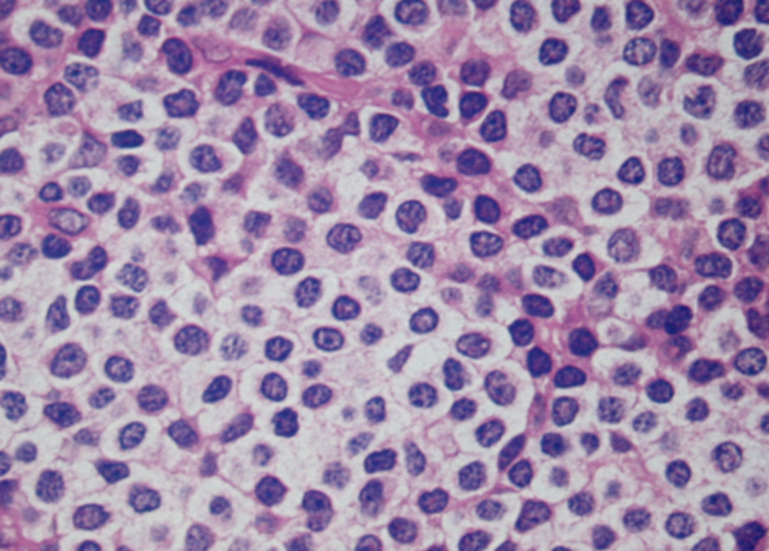

- 核不整のほとんどみられないsmall lymphocytic lymphoma/chronic lymphocytic lymphoma cellと同じ形態の細胞が増殖する症例がある.

- 豊かな蒼白(pale)の細胞質をもつ小型から中型細胞で核と細胞質が表面上末梢単球に類似している。

核は中心性で丸い. わずかに不整がある. 中等度に凝集したクロマチンをもち核小体はめだたない.*1